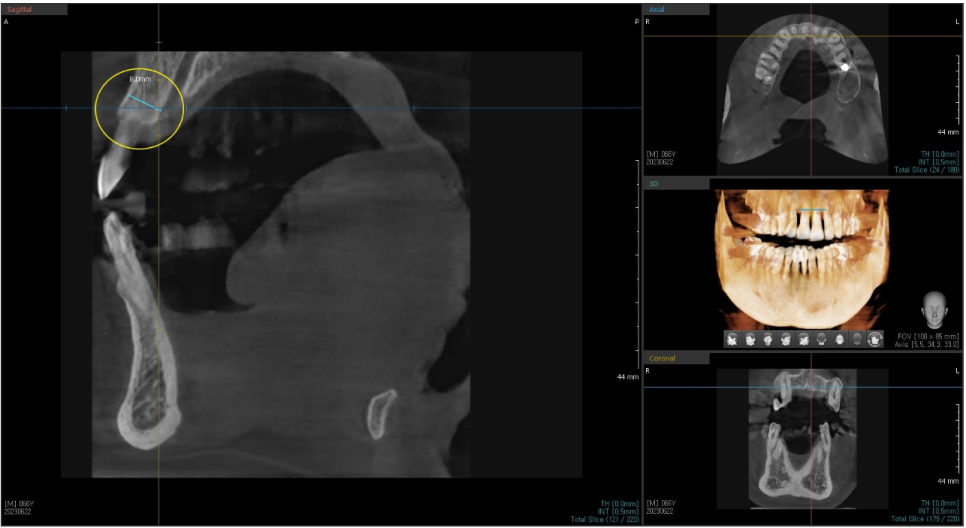

교합 면 쪽에서 바라봤을 때

앞니의 치조골이 푹 들어간 모습을 볼 수 있습니다.

이런 경우

임플란트 식립 시 고정이 잘 안 되는 경우가 발생하기도 합니다.

저희 서울바르디 치과는

수술 이전에 3차원 CT 데이터와 3차원 구강 스캔 데이터를 가지고

모의 수술을 해본 후에 시뮬레이션 결과대로 식립할 수 있게

가이드를 맞춤 제작합니다.

맞춤 가이드를 가지고

식립하기 때문에

정확한 자리의 식립이 가능하고

임플란트 식립 시 생길 수 있는 문제들을 최소한으로 할 수 있습니다.

맞춤 장치를 제작하여 적용하는 방식을 네비게이션 임플란트라고 하는데요.